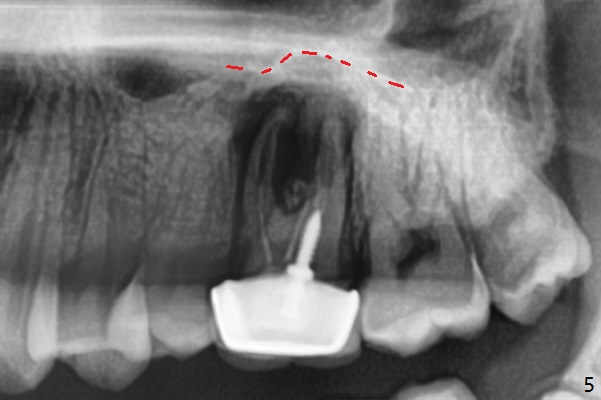

A 29-year-old man has pain in the upper left quadrant. It appears that the tooth #14 has endo and post failure with palatal fistula (Fig.1,2). The septum is almost non-existent; the palatal wall is low, while the sinus floor is present. Sticky bone is placed first against the defective palatal wall and presumably pushed as high as to the sinus floor (Fig.3-5). PRF plug/membrane and 6-month membrane are used to close the socket with 4-0 Chromic gut suture apparently securely, followed by periodontal dressing. Examination of the extracted tooth shows granulation tissue between the roots (Fig.6 *). Underneath the granulation tissue is cement-like material (Fig.7 C). Distal-to-mesial X-ray examination shows possible furcation perforation (Fig.8 *), while mesial-to-distal one the cement-like material in the furca and pulpal chamber as well as MB2 (Fig.9 >). The patient returns 8 days postop, reporting pain reduction, but wants to have #16 extracted. The periodontal dressing is loose, but stuck with 2 sutures underneath. When the dressing is removed, the wound looks normal (Fig.10). In fact the dressing is re-applied. The 6-month membrane has lost 1 month postop. The majority of the socket heals except the palatal (Fig.11 *), as related to the existing palatal fistula/defect (^). Orthodontics is being considered. If the buccal plate collapses 4.5 months post extraction, socket shield should have been done. In fact the buccal plate is robotic, while the bone density is low palatal in CT (Fig.12).